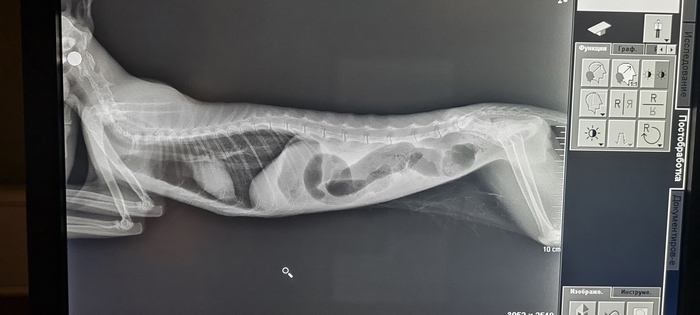

Дела обстоят так: кошка по костям целая, от переломов спас маленький вес (1,8кг). Хоть этаж и был высокий, ничего не сломала. Заработала расщелину нёба и ЧМТ. На лечении все восстанавливается.

Тест на лейкоз отрицательный: